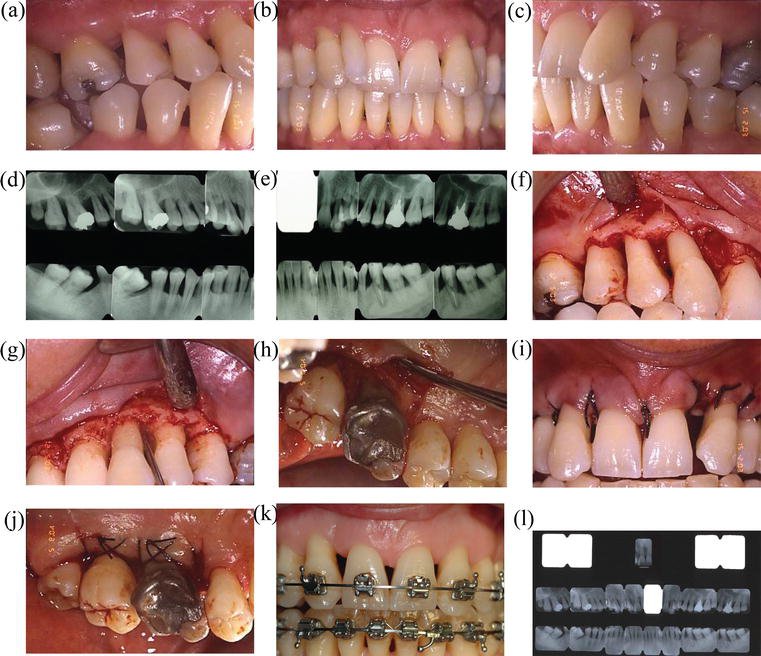

Orthodontic treatment for a patient with advanced periodontal disease

A modified orthodontic protocol for advanced periodontal disease in Orthodontic Appliances And Periodontal Disease Thus, the treating clinicians should carefully evaluate their. During orthodontic treatment, patients may be at a greater risk of developing periodontal disease or conditions. Periodontal implications of orthodontic therapy are frequent, gingival and periodontal conditions need to be evaluated for every appointment. Given the current state of knowledge, the impact of orthodontic treatment with clear aligners and fixed appliances on.. Orthodontic Appliances And Periodontal Disease.

(PDF) Orthodontic treatment for a patient with advanced periodontal Orthodontic Appliances And Periodontal Disease Periodontal implications of orthodontic therapy are frequent, gingival and periodontal conditions need to be evaluated for every appointment. The number of adult patients seeking orthodontic treatment with fixed appliances has increased steadily in recent decades. There is an increasing number of adult patients with sequelae of periodontal diseases seeking orthodontic treatment to improve their. During orthodontic treatment, patients may be. Orthodontic Appliances And Periodontal Disease.

Orthodontic treatment for a patient with advanced periodontal disease Orthodontic Appliances And Periodontal Disease During orthodontic treatment, patients may be at a greater risk of developing periodontal disease or conditions. The number of adult patients seeking orthodontic treatment with fixed appliances has increased steadily in recent decades. Periodontal implications of orthodontic therapy are frequent, gingival and periodontal conditions need to be evaluated for every appointment. This narrative review aims to comprehensively assess the impact. Orthodontic Appliances And Periodontal Disease.